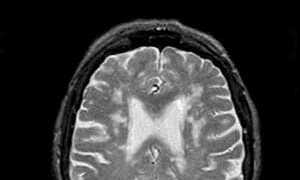

МРТ

Современным и наиболее точным методом диагностики остается магнитно-резонансная томография (МРТ). Процедура осуществляется с использованием специализированного томографа, который работает на основе регистрации реакций клеток организма на воздействие мощного магнитного поля.

Данный метод позволяет получить детальную информацию о структуре внутренних органов, включая сосудистую систему. МРТ считается абсолютно безопасным, так как это неинвазивная процедура, не требующая применения радиоактивного облучения.

Что означает на МРТ вариант развития Виллизиева круга?

Если МР-сигнал от видимых сосудов Виллизиева круга гиперинтенсивен, это означает, что препятствий для движения крови нет. Сниженная интенсивность МР-сигнала свидетельствует о замедлении кровотока либо о его полном отсутствии.